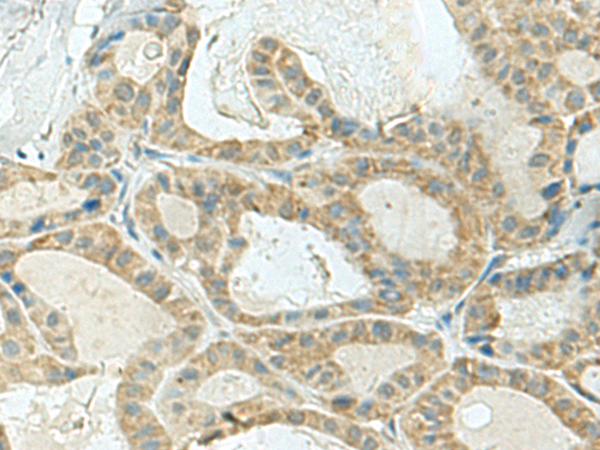

分类: 科研抗体货号: P10185别名: PROLIDASE应用: WB,IHC反应种属: Human, Mouse, Rat